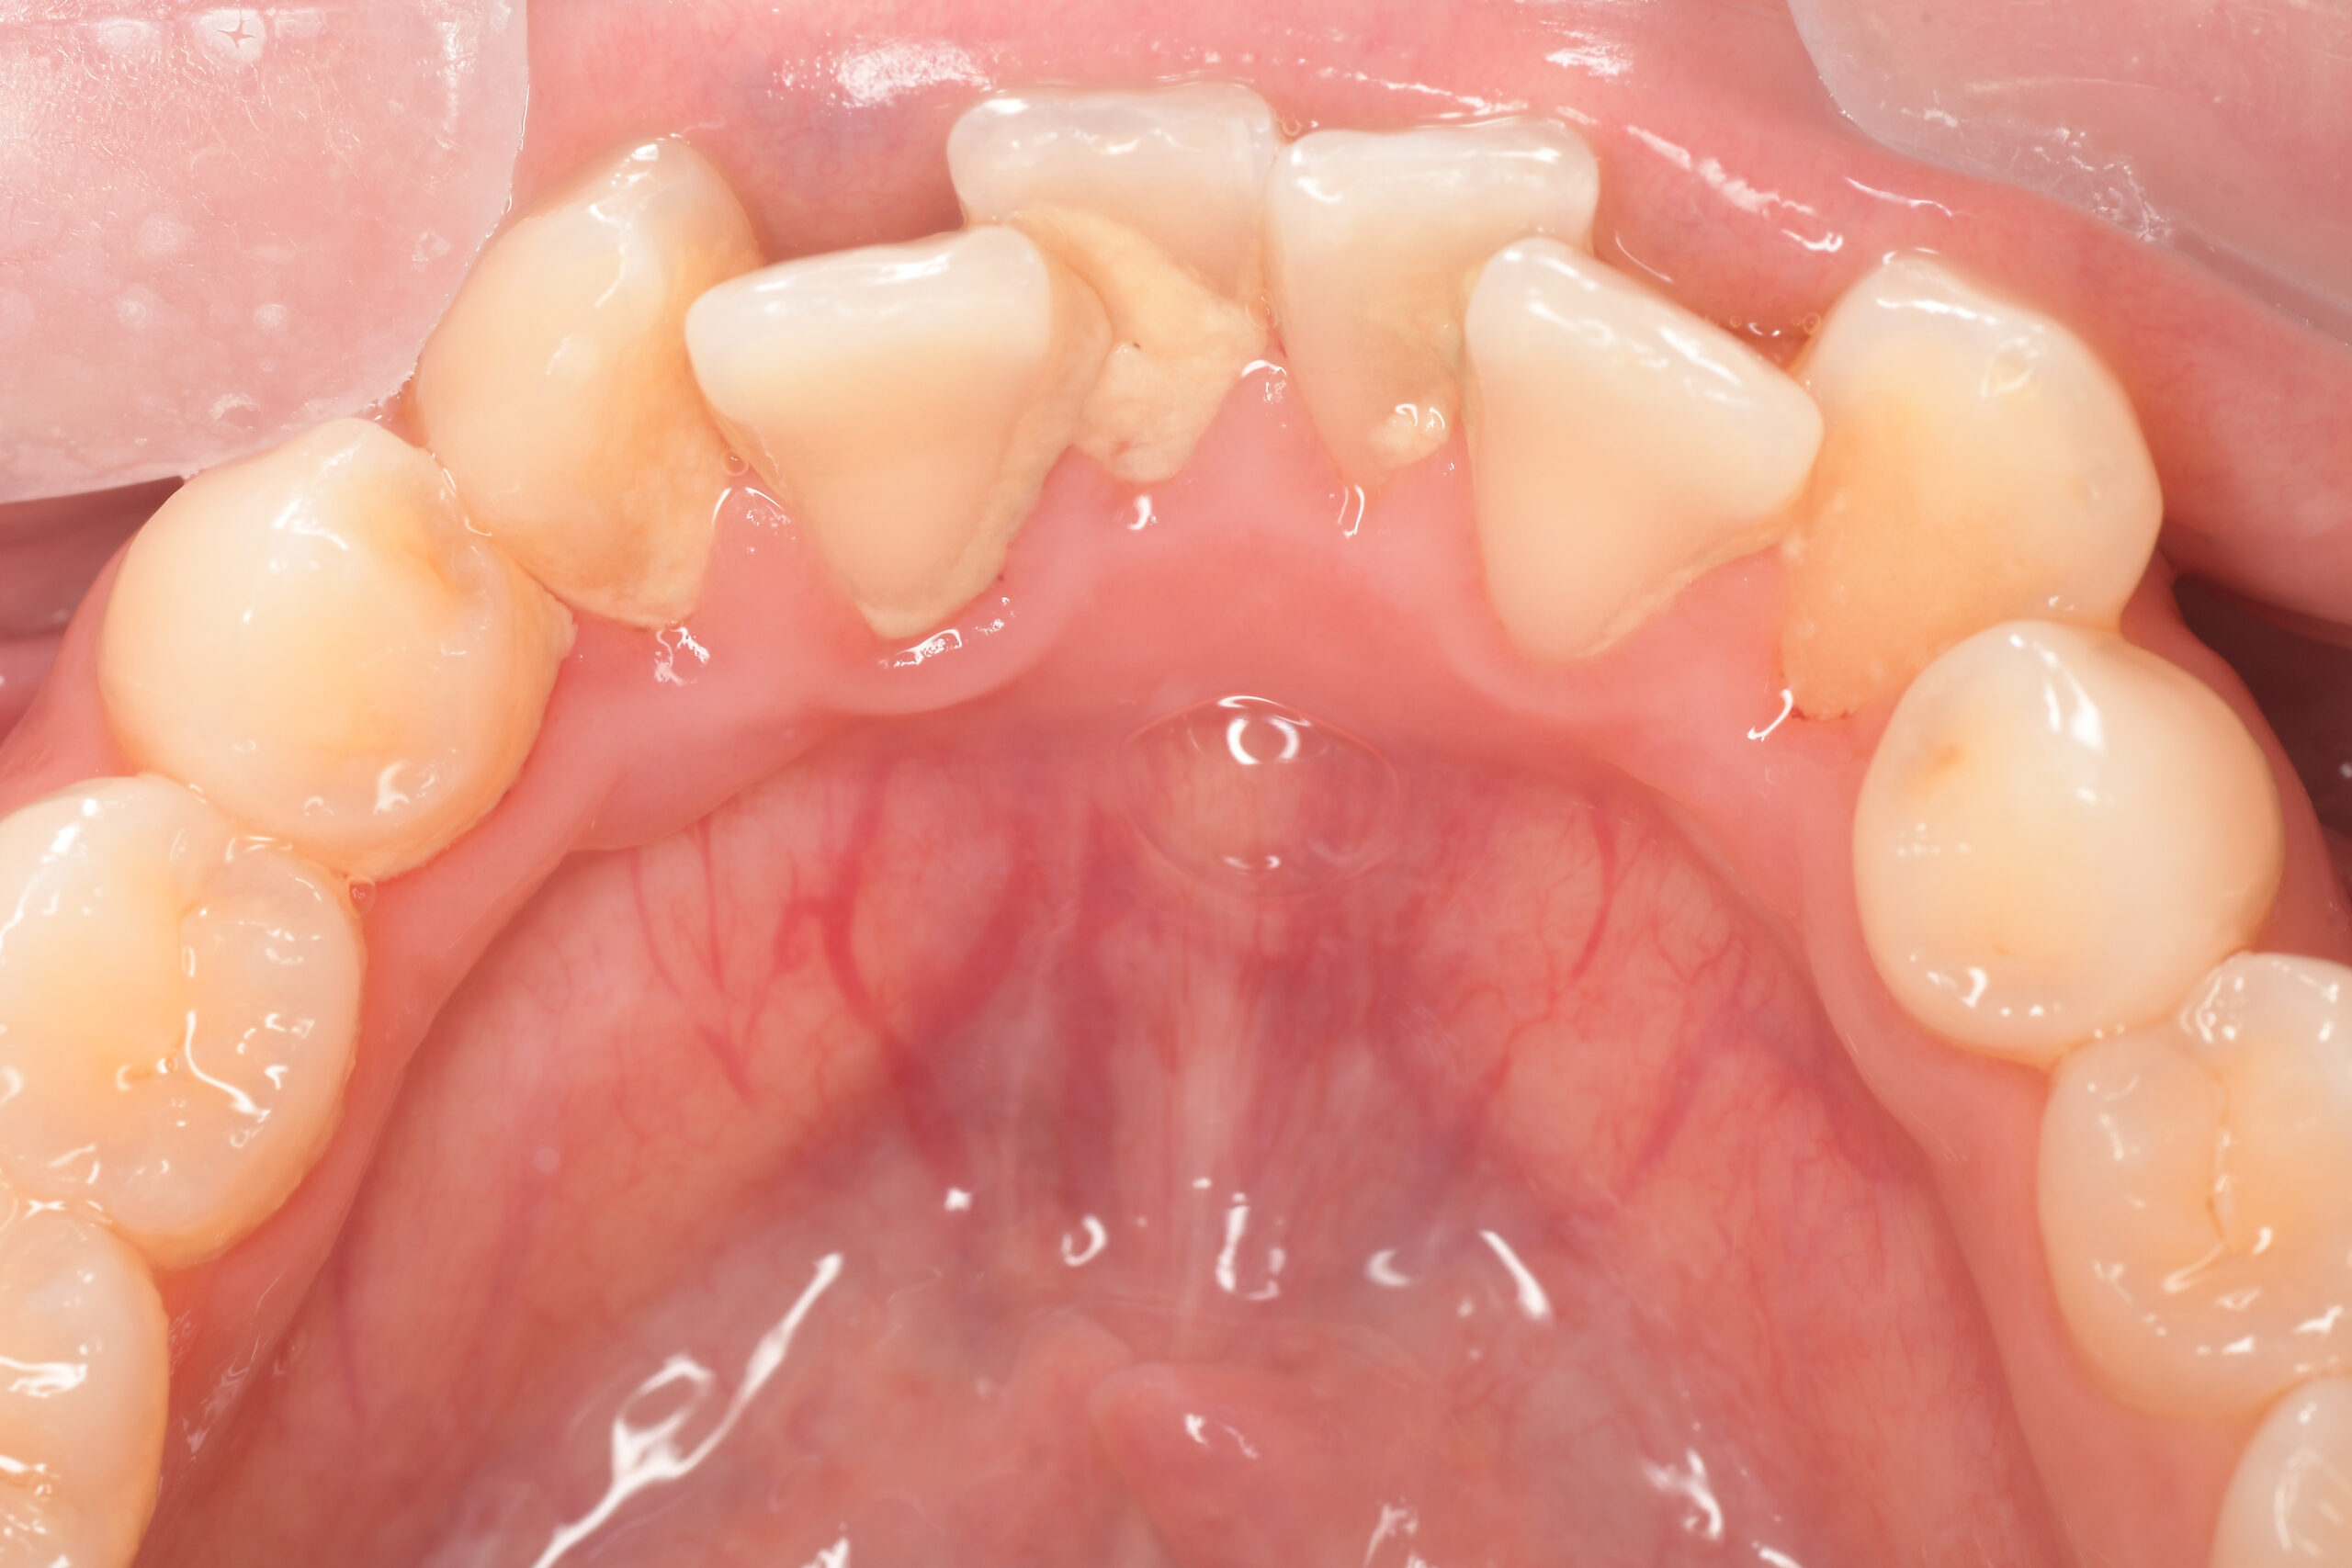

CASE 10

Before①

After①

Before②

After②

基本情報

| 年齢・性別 | 38歳・男性 |

| 主訴 | 下顎 歯石除去したい |

| 治療内容 | スケーリング |

| 治療期間 | 30分 |

| 治療費 | 約1,500円(保険診療) |

| リスク・副作用 | 知覚過敏、歯肉退縮 |

| 治療方針 | 歯肉縁上歯石を除去してから歯肉縁下歯石を除去します。ご自身でのプラークコントロールができるようになったら定期検診に移行します。 |

| 担当者所見 | 半年ぶりの歯科医院の受診。歯石が付きやすいためセルフケアの重要性をお伝えして、定期的にクリーニングを行います。出血率が高く炎症が強いため、今後はセルフケアを強化して歯周病治療を行います。 |